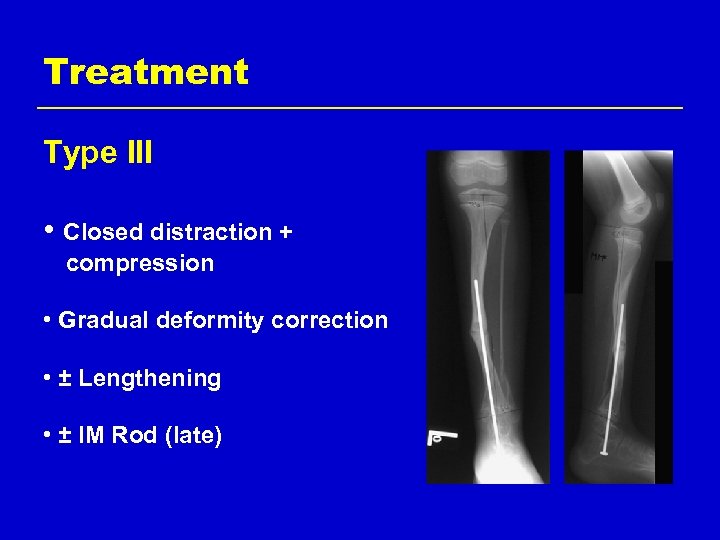

Treatment Type III • Closed distraction + compression • Gradual deformity correction • ± Lengthening • ± IM Rod (late)

Treatment Type III • Closed distraction • Gradual deformity correction • ± Lengthening • ± IM Rod (late)